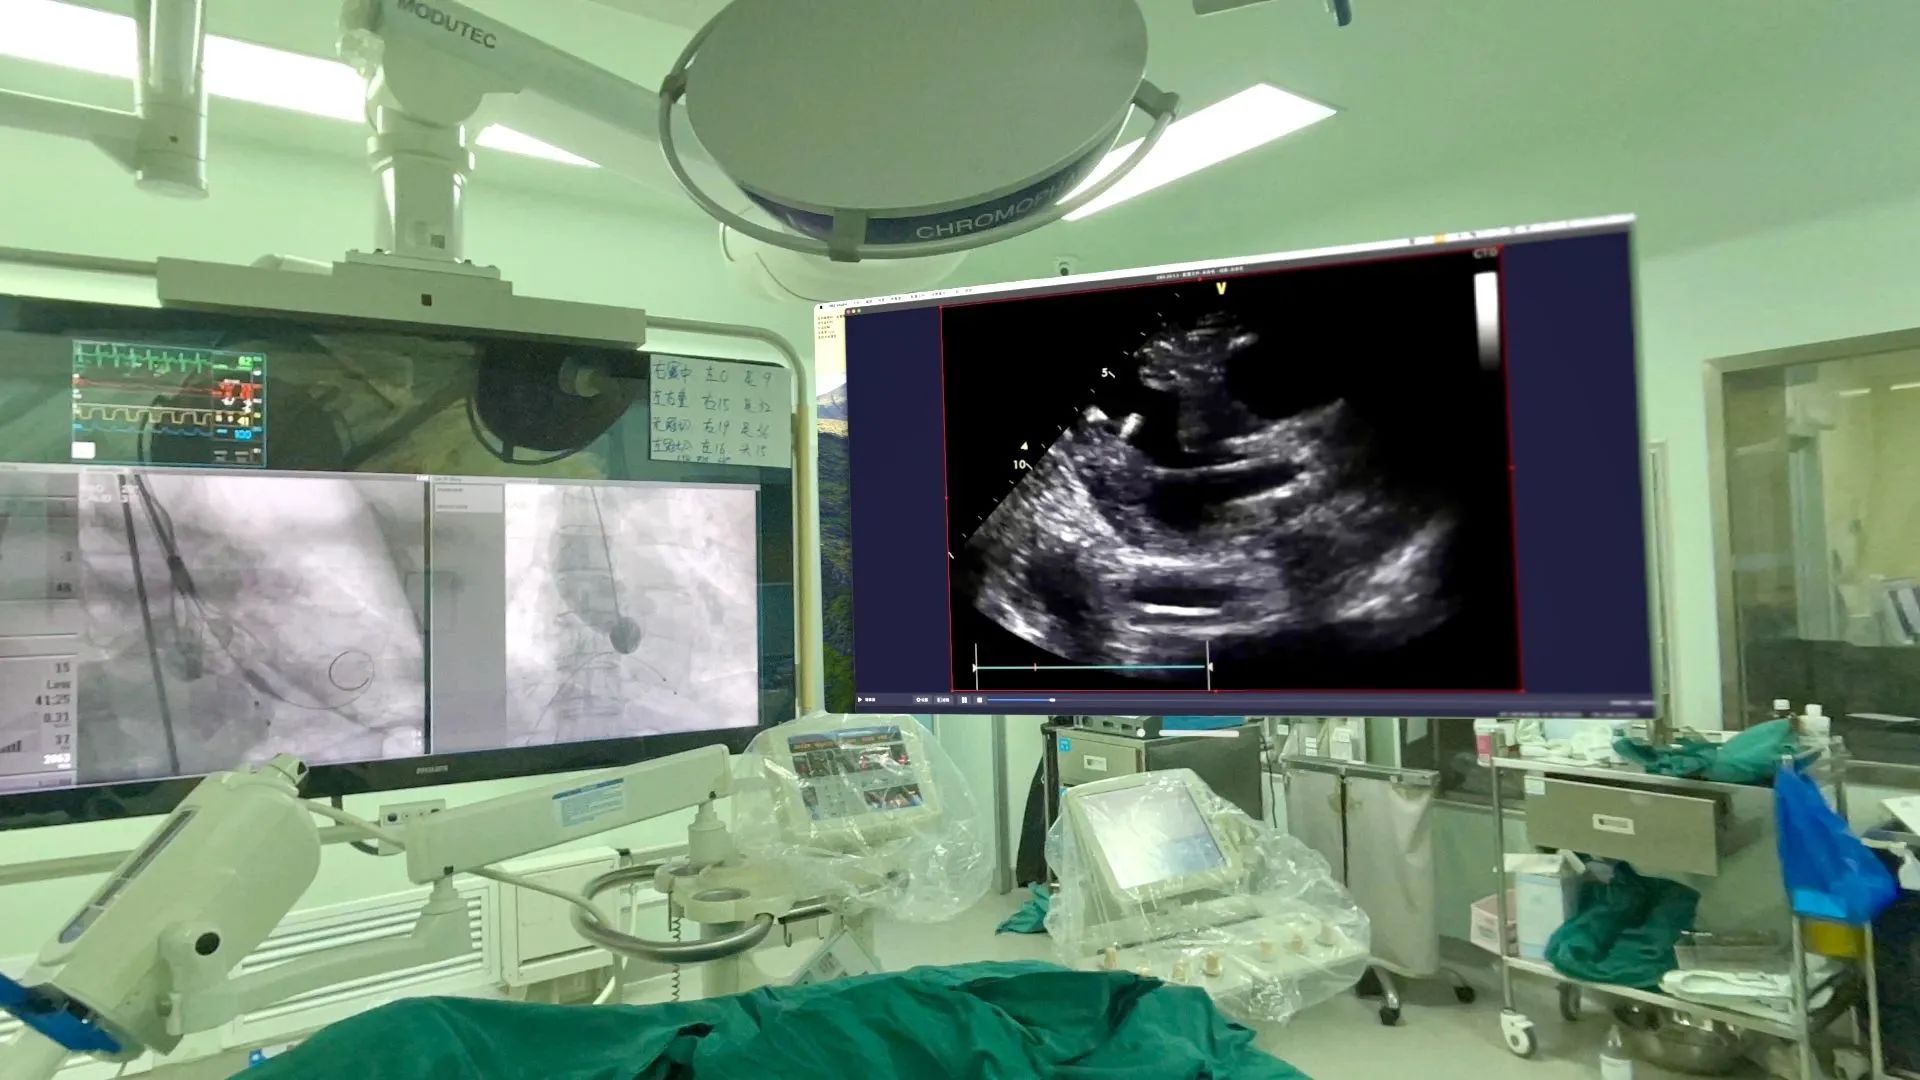

2 其次在术中,团队可以利用该设备先进的增强现实技术,通过高清晰度、大视野的虚拟屏幕向术者呈现极低延时(约50ms)的超声图像,提高了手术操作的精准度和安全性。而以往在术中,术者往往需要停下手术操作、来到超声机屏幕前观察;即使超声机外接屏幕,也存在视野小、挤占手术室空间等问题。因此Apple Vision Pro头显完美解决了术者的用户痛点。且术者可以通过手势操作控制虚拟屏幕的尺寸及位置,不需要触碰机器、不违背无菌操作原则。

TAVR术中场景,左侧为DSA机器悬吊屏幕,右侧为Apple Vision Pro头显的虚拟屏幕